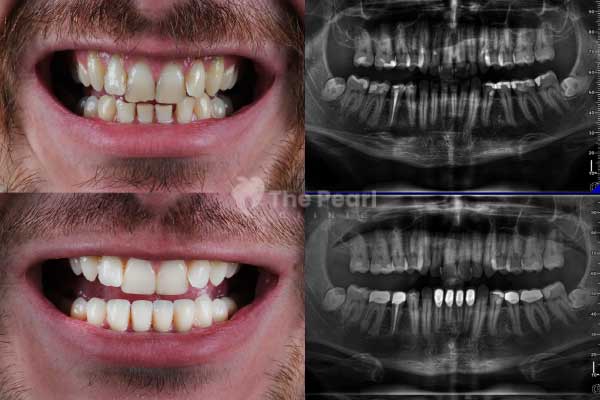

A filling, also known as a dental filling, is the most commonly used treatment method in the early stages of cavity treatment. It involves removing the affected tissue and leaving a space to be filled with a biocompatible material later. This process rehabilitates the damaged part of the tooth, restoring its functionality and original appearance.

There was a time when smiles were filled with silver and even gold decorations. In the past, highly durable silver amalgam materials were used. However, their negative aesthetic effects have led to the adoption of newer materials. Primarily, we refer to composites. These are a type of resin that matches the color of the bone like the tooth. As mentioned earlier, composites fill the void, and since they harden with light, they are cured with a special light.

The downside is that composites are less durable than metal fillings. However, this does not mean you have to change your fillings every week. During periodic check-ups, the dentist will tell the patient when the old filling needs to be replaced. Depending on the patient's care, bite, and other personal conditions, a composite filling can last for many years.